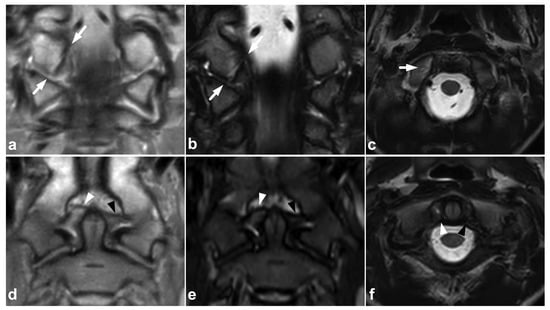

Figure 4.

(a) Coronal PD-weighted. (b) Coronal T2-weighted. (c) Axial T2-weighted. (d) Coronal PD-weighted. (e) Coronal STIR. (f) Axial T2-weighted. A 13-year-old male, motor vehicle accident. Avulsion fracture (arrows) of the right alar ligament origo in the occipital condyle, minor dislocation. The right alar ligament (white arrowheads) is swollen and loose but not completely torn. An intact left alar ligament is marked with black arrowheads.